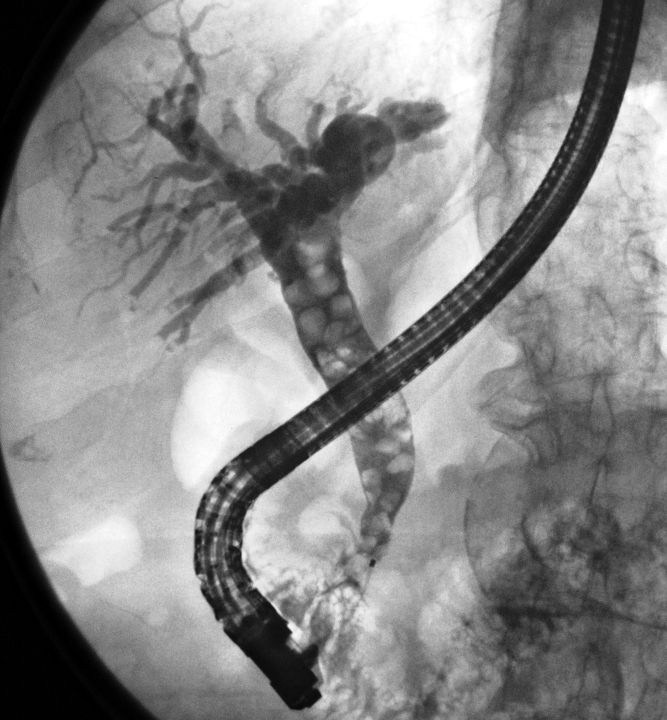

Die ERCP (endoskopisch retrograde Cholangio-Pankreatikographie) ist eine Untersuchung der Gallengänge und des Bauchspeicheldrüsengangs. Dazu wird ein biegsames optisches Instrument (Duodenoskop) über die Mundhöhle, Speiseröhre und Magen in den Zwölffingerdarm vorgeschoben. Dort befindet sich die Mündung von Gallen- und Bauchspeicheldrüsengang, die hierbei mittels Röntgen untersucht werden kann.

Die Untersuchung wird in Bauchlage durchgeführt. Aus Sicht des Patienten ähnelt sie der Magenspiegelung, allerdings wird das Endoskop tiefer in den Zwölffingerdarm platziert, so dass die Gallengangsmündung (Papille) zu sehen ist. In diese wird Kontrastmittel eingespritzt, und so die Gallengänge unter Röntgendurchleuchtung sichtbar gemacht. Ist beispielsweise ein Abflusshindernis in den Gängen durch Gallensteine vorhanden, kann dies nun endoskopisch mit verschiedenen Methoden beseitigt werden.